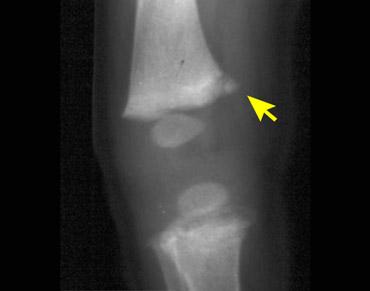

Gãy xương góc (Corner fracture)

Gãy xương góc hành xương, còn được Kleinman gọi là tổn thương hành xương kinh điển, lần đầu tiên được mô tả bởi Caffey, người đã ghi nhận những gãy xương đặc biệt này ở trẻ em có tụ máu dưới màng cứng. Chúng thường xuất hiện hai bên và ở đầu dưới xương chày, thường gặp hơn ở phía trong.

Khi một mảnh xương nhỏ bị bong ra do lực cắt tác động lên sụn tăng trưởng mỏng manh, nó được nhìn thấy như hình ảnh gãy xương góc điển hình. Những gãy xương này phổ biến nhất ở xương chày, đầu dưới xương đùi và đầu trên xương cánh tay. Chúng thường xuất hiện hai bên.

Những gãy xương này thường rất kín đáo, và khả năng phát hiện phụ thuộc trực tiếp vào chất lượng của các nghiên cứu hình ảnh.

Hình ảnh

Gãy xương kiểu tay xách xô ở đầu trên xương chày. Mảnh gãy hành xương được nhìn thấy như hình đĩa hoặc tay xách xô.